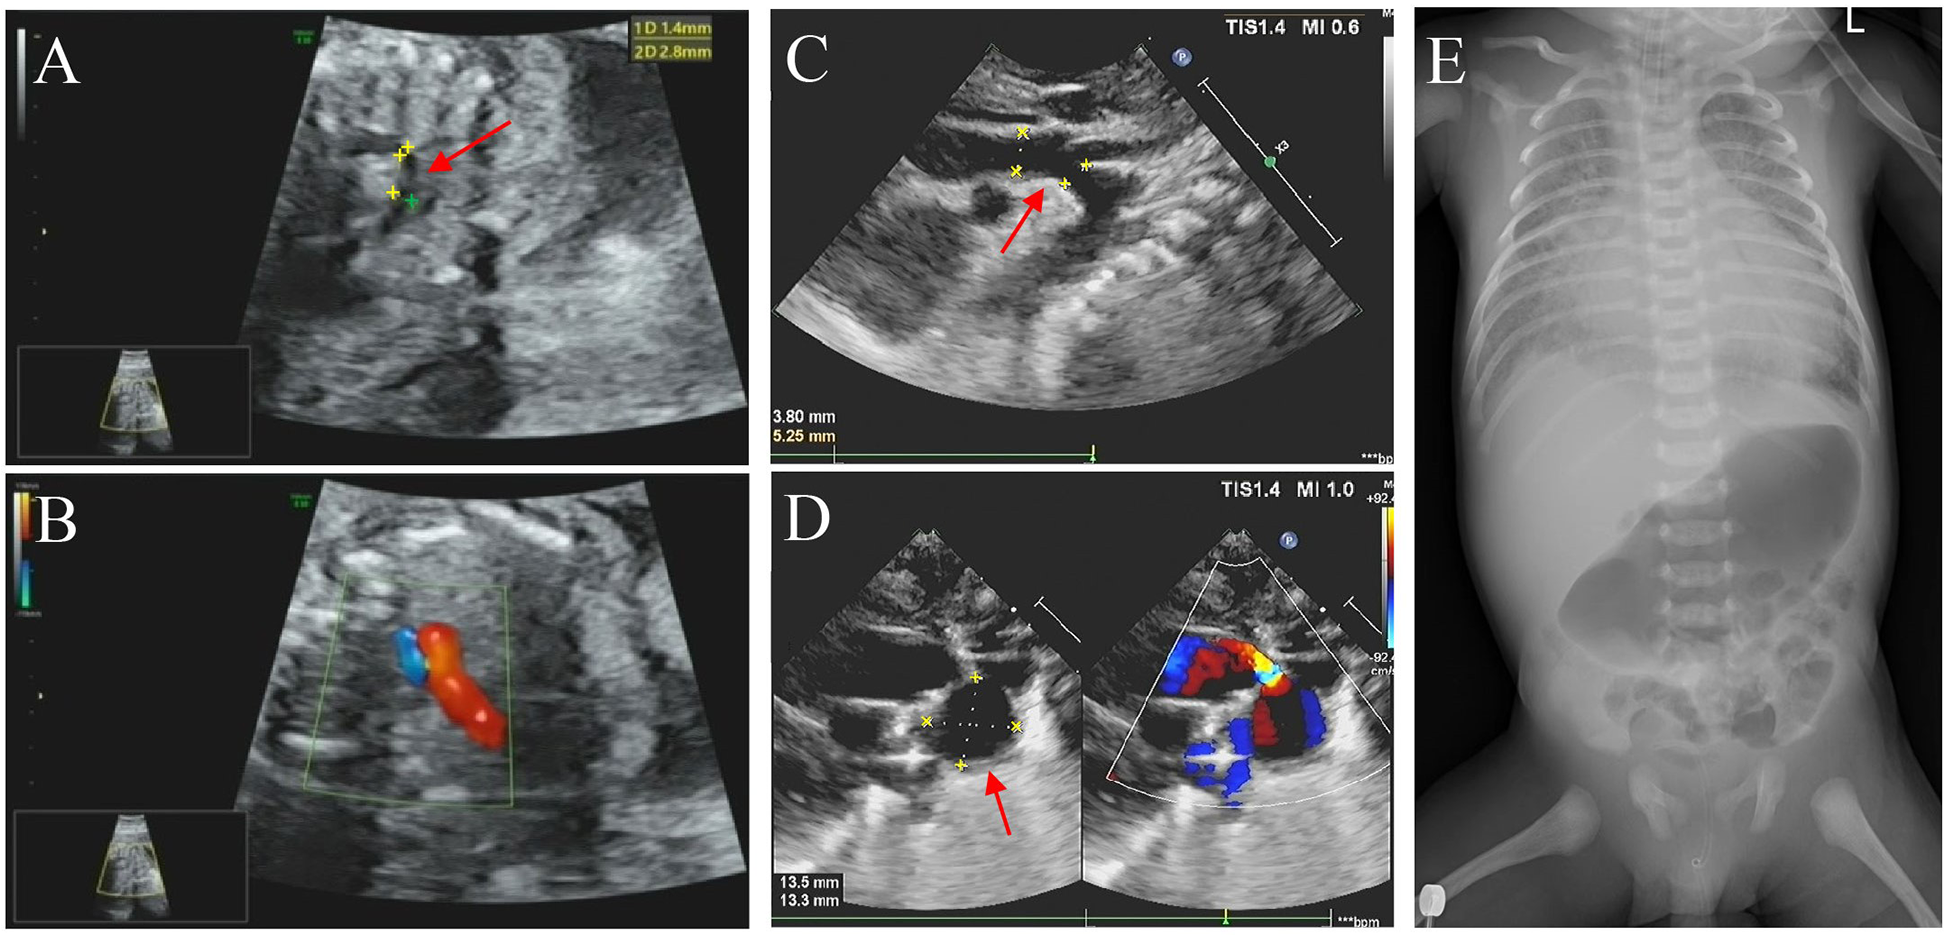

In this family, the father is of Han Chinese descent, while the mother belongs to the Miao ethnic minority group in China. The parents denied a consanguineous marriage and have a healthy daughter. No family history of genetic disorders was reported. The proband was a male fetus, the second child of the 26-year-old mother (gravida 5, para 2). He was diagnosed with CHD in utero at 25 weeks of gestation. Fetal echocardiography revealed several cardiac abnormalities, with a normal cardiac rate (144 bpm); these abnormalities included aortic stenosis with coarctation of the aortic arch (from aortic root diameter measuring 2.3 mm to an isthmus of 1.7 mm), mitral valve regurgitation with reduced mitral valve flow, a patent foramen ovale (left-to-right shunt), an enlarged left atrium (left 13 mm × 13 mm vs. right 11 mm × 11 mm), and an enlarged right ventricle (right 14 mm × 11 mm vs. left 15 mm × 8 mm) (Figures 1A,B). The mother did not terminate the pregnancy despite the obstetrician informing her of the risks. At 39 weeks of gestation, the obstetrician reported no other abnormalities except the CHD.

Ultrasound and X-ray images of the proband. Images A, B, C, and D show the echocardiography of the proband. In images A and C, the red arrowhead points out the coarctation of the aortic arch during the fetal period and the neonatal period, respectively. Image B shows pulmonary and aortic blood flow incongruity with an increased vessel ratio. Image D shows a patent ductus arteriosus aneurysm (marked with an arrowhead) and a bidirectional arterial shunt. Image E is an X-ray of the proband's torso, showing the ribcage and spine with no obvious abnormalities.

Figure 1. Imaging examination results. (A,C) Echocardiography performed during the fetal period (25 weeks pregnant) and neonatal period, respectively, showed the coarctation of the aortic arch (marked with an arrowhead). (B) The fetus exhibited pulmonary and aortic blood flow incongruity with an increased vessel ratio. (D) Neonatal imaging showing a patent ductus arteriosus aneurysm (marked with an arrowhead) and a bidirectional arterial shunt. (E) Digital x-ray imaging did n't show any obvious developmental abnormalities of the sternum, ribs, or spine.

The proband was delivered with normal growth parameters (birth weight = 3,130 g, length = 50 cm) by cesarean section at 40 weeks of gestation due to severe preeclampsia and then transferred to neonatology for respiratory distress. Imaging examinations did n't reveal any significant developmental anomalies of the sternum, ribs, or spine, but they did reveal more severe CHD symptoms, including an atrial septal defect (3.9 mm), a patent ductus arteriosus aneurysm (DAA, 14 mm × 13 mm aneurysm), aortic stenosis, aortic arch dysplasia (3.8 mm), moderate mitral regurgitation, an enlarged right ventricle (right 30 mm × 15 mm vs. left 27 mm × 16 mm), and an enlarged left atrium (left 26 mm × 23 mm vs. right 23 mm × 19 mm) with reduced left ventricular systolic function (Figures 1C–E). On the ninth day of life, the proband was transferred to the neonatal intensive care unit (NICU) due to heart failure (N-terminal BNP >5,000 pg/ml, troponin = 2.450 μg/L), respiratory failure, gastrointestinal bleeding, and cardiogenic shock accompanied by metabolic disorders (hypoglycemia, hyperlactatemia, and hyperkalemia). Life support measures were initiated, including ventilator-assisted ventilation, milrinone injection, alprostadil injection, and nutritional support therapy. Although medical treatment improved his metabolic acidosis and internal hemorrhage, the proband unfortunately died prematurely within a month due to heart failure.